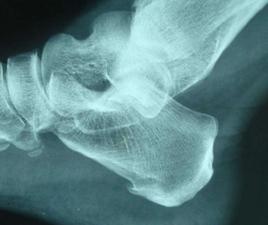

足跟骨刺易發人群是中老年人群,因為隨著年齡的增長,足跟長期、慢性的磨損,同時足跟是人類承受壓力最大持續時間最久的部位,老年人的足跟不知經歷了多少難以計數的磨擦和衝擊,所以很多老年人容易發生足跟骨刺。據臨床觀察,有的老人是兩足同時或先後發病,但大部分發生在單側。而一般在早晨起床剛下地走動時疼痛較重,走一會兒疼痛反而減輕,長途步行引起勞累後疼痛又會加重,如走路時不慎踩在磚瓦塊上或下樓梯時,足部著地用力過猛,會引起劇烈疼痛。有時在足跟中央有一個壓痛點,用手指觸壓疼痛劇烈。X光片顯示跟骨有骨贅形成。